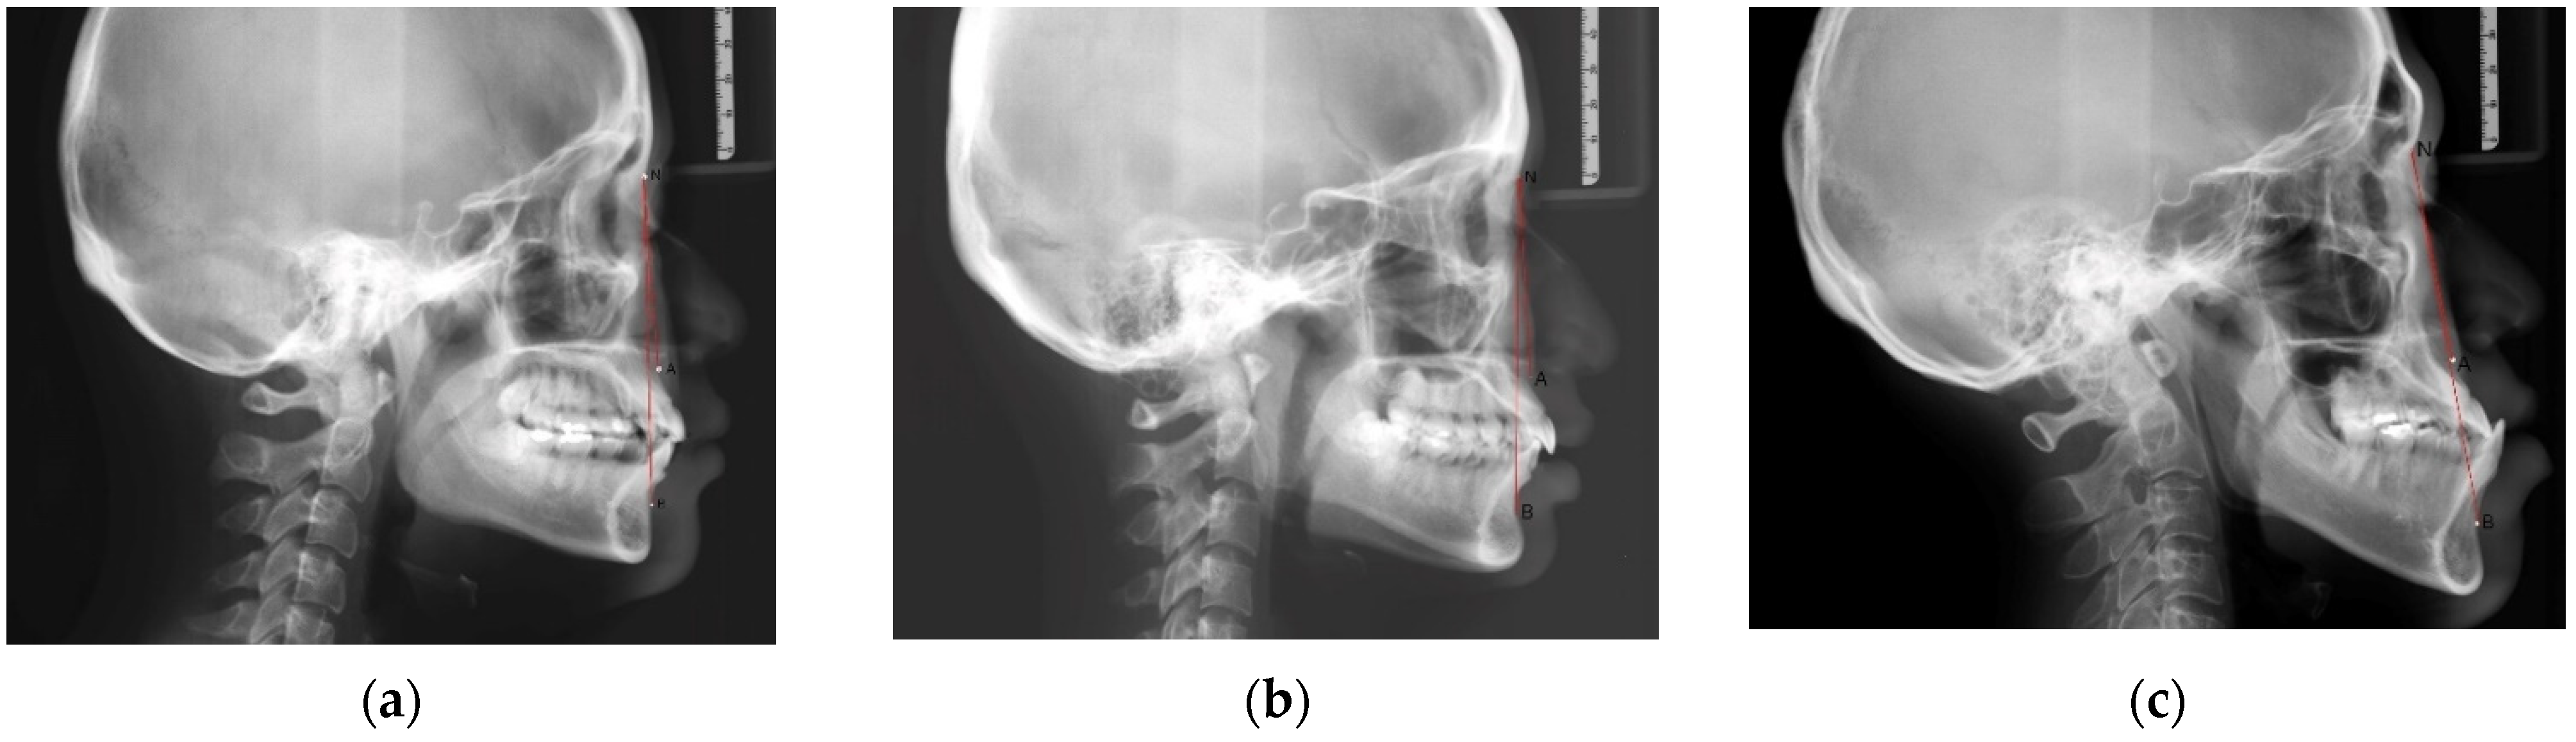

2.3. Assessment of the Sagittal Skeletal Relationship

The anterior-posterior skeletal relationship between the maxilla and the mandible of the orthodontic patient was classified as Class I, Class II, or Class III (Figure 1 and Figure 2) according to Steiner’s [8] and Tweed’s [9] analyses (Table 1).

Figure 1. The landmarks used to analyze lateral cephalometric radiographs.

Figure 2. The sagittal skeletal relationship was classified as Class I, Class II, or Class III based on the ANB angle, which was formed by the A point, Nasion, and B point: (a) Class I relationship: ANB angle was 2–4 degrees; (b) Class II relationship: ANB angle was larger than 4 degrees; (c) Class III relationship: ANB angle was smaller than 2 degrees.